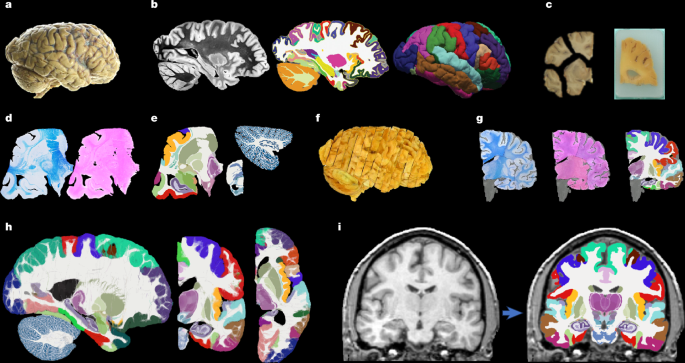

A probabilistic histological atlas of the human brain for MRI segmentation

Brain specimens

Hemispheres from five individuals (including half of the cerebrum, cerebellum and brainstem), were used in this study, following informed consent to use the tissue for research and the ethical approval for research by the National…